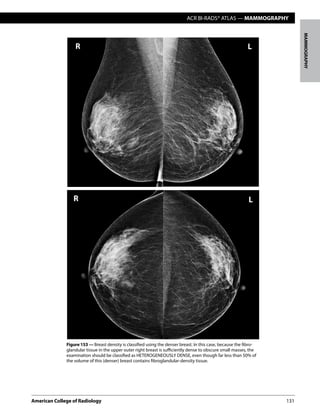

Figure 153 — Breast density is classified using the denser breast. In this case, because the fibro-

glandular tissue in the upper outer right breast is sufficiently dense to obscure small masses, the

examination should be classified as HETEROGENEOUSLY DENSE, even though far less than 50% of

the volume of this (denser) breast contains fibroglandular-density tissue.